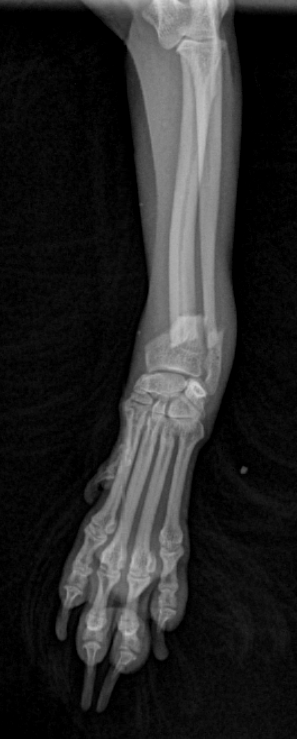

Fracture Salter-Harris sur un chaton Européen de 10 mois

Spike, chaton européen mâle de 10 mois, a été présenté en consultation pour boiterie du membre postérieur droit à la suite d'une chute depuis le 1er étage.

A la radiographie, une fracture de type Salter-harris 1 est diagnostiquée, avec déplacement de l'about discal.